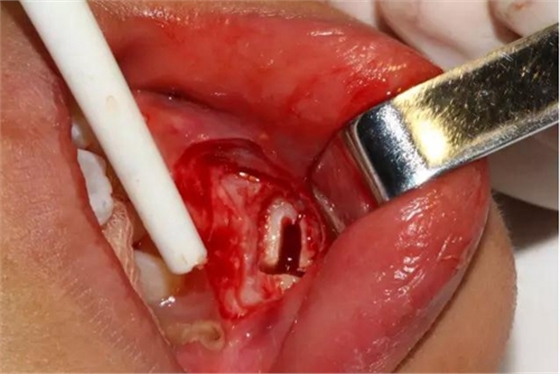

切開、翻瓣

去除骨皮質,暴露牙冠大部分

設計冠切的位置